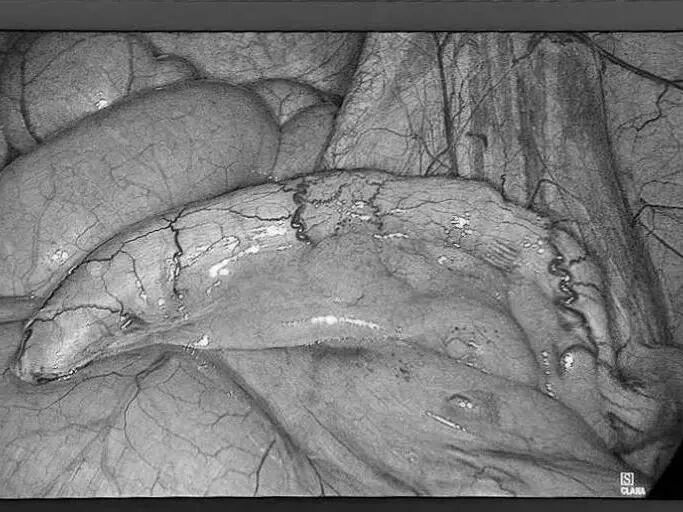

一名女性患者长期受到下腹部坠胀、排便不适等症状困扰,近期发现盆腔内存在肿物,严重影响其生活质量,为寻求进一步诊治,她前往贵州航天医院普外科就诊,经核磁共振(MRI)检查提示:盆腔内直肠与骶骨之间有一个“骶前囊肿”。由于该囊肿位置深,且与周围重要的神经和血管关系密切,若采用传统手术不仅创伤大,还伴随一定的风险。 面对这一棘手难题,普外科立即组织了麻醉科、医学影像科、妇科、重症医学科在内的多学科专家会诊(MDT)。经专家团队详细评估,与患者及家属充分沟通后,为患者制定并成功实施了“腹腔镜下骶前囊肿切除术”。术后恢复良好,不久便康复出院。 【疾病科普|什么是骶前囊肿?】 骶前囊肿,可以理解为生长在骨盆最深处、直肠后方的一个囊性肿物。由于它“躲藏”的位置非常特殊,四周紧邻着控制排便和感觉的重要神经与血管,因此被视为盆腔外科手术中的一个难点。 它可能带来哪些影响? 1.随着囊肿逐渐增大,可能会压迫直肠,引起排便困难或坠胀感。 2.压迫骶神经,可能导致腰骶部或会阴区的酸胀、疼痛。 3.囊肿本身也可能发生感染,形成脓肿,加重不适。 【技术介绍|腹腔镜下骶前囊肿切除术】 对于骶前囊肿这类较深的病灶,腹腔镜下骶前囊肿切除术提供了一种更为微创、便于操作的解决方案。 它是如何进行的? 医生仅通过腹部几个约0.5-1厘米的小孔,其中一个孔放入带高清摄像头的腹腔镜,将盆腔内的景象放大并清晰地投射到屏幕上,如同给了医生一双进入体内的“眼睛”。其他几个小孔则伸入细长的专用手术器械。医生看着屏幕,遥控这些器械,在清晰的视野下精细地分离并完整切除囊肿。 腹腔镜微创手术的特点包括: ▶创伤较小:避免了传统手术的长切口,体表疤痕小。 ▶视野清晰:放大后的图像让医生能更清楚地分辨囊肿与周围重要结构。 ▶操作精准:有助于更完整地切除囊肿,并尽力保护盆腔神经功能。 ▶恢复较快:因手术创伤小,患者术后疼痛感更轻,下床活动早,住院时间也可能缩短。 注:本文旨在进行健康科普,分享医疗案例与科普知识,不能替代任何专业的医疗建议。如有任何健康问题,请务必及时咨询并遵从专业医生的诊疗意见。 贵州航天医院普外科专家简介 高大勇 普外科(肛肠外科)学科带头人、名誉主任,主任医师、教授 临床擅长:对中西医结合诊治肛肠学科各种常见病、多发病及疑难杂症等具有丰富的临床经验。 原遵义市第一人民医院(遵义医科大学第三附属医院)、遵义市中医院肛肠科主任。中华中医药学会肛肠分会常委,全国中医肛肠学科名专家,中国健康促进与教育协会肛肠分会常委,中国康复医学会肛肠疾病康复专业委员会常委,中国民间中医医药研究开发协会肛肠分会副秘书长,中国医师协会中西医结合肛肠医师专业委员会常委,国家二级心理咨询师,贵州省第一批中医名医工作指导老师,遵义市名中医,遵义市肛肠学会会长,遵义市肛肠质控中心名誉主任,遵义市中西医结合学会名誉会长,遵义市健康科普专家,原贵州省中西医结合学会肛肠分会副主任委员、贵州省中医肛肠质控中心副主任、遵义市医学会医疗鉴定委员会专家、遵义市卫生系列高级评委。发表论文30余篇,主编和参编医学著作5本,主持省级科研课题2项、市级科研课题2项、院级科研课题1项。 梁 跃 普外科党支部书记、主任,主任医师 临床擅长:对普外科各类肿瘤手术具有丰富的临床经验。 毕业于遵义医学院,遵义市医学会小儿外科学分会常务委员,遵义市肛肠协会理事,遵义市医学会核医学分会(第二届)委员会委员;荣获第三期“黔医人才计划”优秀学员称号;主持市级课题1项,完成省级课题1项,在国内各类刊物上发表论文10余篇。 钱科洪 民盟盟员,普外科副主任医师 临床擅长:从事普外科临床工作30余年,对各类普外科疾病的诊治、乳腺、甲状腺、胃十二指肠、结直肠等疾病及疑难杂症具有丰富的临床经验。 毕业于遵义医学院临床医疗系,2009年前往中山大学附属第一医院微创外科进修学习,在国内各专业期刊发表论文数篇。 贵州航天医院普外科简介 基本情况 贵州航天医院普外科成立于1968年,前身属于原航天部O61基地3417医院外一科,1998年3417医院、3427医院合并后更名为普外科,下设胃肠外科、肛肠外科2个亚专业科室,拥有在全市较为先进的专科设备和技术,是中国疝病专科联盟单位,贵州医科大学附属医院胃肠外科专科联盟单位。开放床位40张,配备医护人员21人。 专科特色 普外科致力于胃肠及肛肠疾病的外科临床诊治及科研,以腹腔镜微创外科技术为本,形成以快速康复治疗胃肿瘤、结直肠肿瘤、小肠肿瘤、直肠脱垂、肥胖病、急腹症、各类疝、痔、瘘等专科特色,同时注重胃肠疾病尤其是结直肠恶性肿瘤的基础研究和临床转化研究,总体诊断和治疗水平在区域同级医院居于领先水平。 开展手术:腹腔镜下胃癌根治术,腹腔镜下袖状胃切除术,腹腔镜下胃肠道间质瘤切除术,腹腔镜下结、直肠癌根治术,胃癌、结直肠癌的精准治疗,腹腔镜下小儿疝气、成人疝修补术,腹腔镜下阑尾手术,内痔的硬化注射治疗及痔疮的微创治疗:ATH、PPH、TST,直肠脱垂的各种手术治疗,难治性伤口VSD技术,鼻胃肠管、肠梗阻导管置入术,肛肠术后间歇性导尿技术,并引进了中医适宜技术,也为各种化疗患者提供输液港安装,提高患者就医体验。 腹腔镜下腹股沟疝 无张力修补术 腹股沟疝里金斯坦 (Lichtenstein)手术 PPH微创术治疗环状混合痔 黏连性或炎性肠梗阻-肠梗阻导管 腹腔镜袖状胃切除 腹腔镜阑尾切除术 腹腔镜阑尾肿瘤切除术 腹腔镜下结肠癌根治术 诊疗范围 胃肿瘤、结直肠肿瘤、小肠肿瘤、肥胖症、各类急腹症、腹部外伤、腹壁疝、便秘、直肠脱垂、痔疮、肛瘘、肛裂等胃肠、肛肠外科疾病。 END